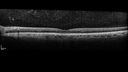

Paclitaxel induced cystoid macular edema - reversed when chemo stopped25 views74 year old retired physician About 2-3 weeks ago there was gradual vision loss in the right eye. The patient was seen by an ophthalmologist who saw macular swelling and injected vabysmo. He has been on chemotherapy (Carbiplatin and Carboxytaxol for 2 cancers - advanced prostrate diagnosed 2019 - has had brain surgery AND squamous lung cancers treated with radiation)

Medical Hx: Prostate cancer (Onset: 2018). Pulmonary and bone cancer metastatic. Brain cancer metastasized from prostate cancer.

Surgical Hx: Right frontal & Frontoparietal Craniotomy (Onset: 2024). Appendectomy. Hemorrhoidectomy. Herniorrhaphy. Prostate. Systemic Meds: Chemotherapy. Radiation. Eligard Every 3 Months 22.5 MG per 0.375 ML Prefilled Syringe. MIRALAX prn. Tums Freshers 500 MG Chewable Tablet. Vitamin D. XGEVA.

VA OD: Dcc20/125+1

VA OS: Dcc20/125-2

TP: OD:12 OS:15Aug 17, 2025